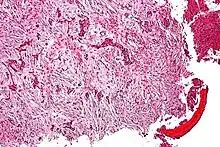

It involves both epithelial and osteofibrous tissue.[1] Histologically, islands of epithelial cells are found in a fibrous stroma.[9]